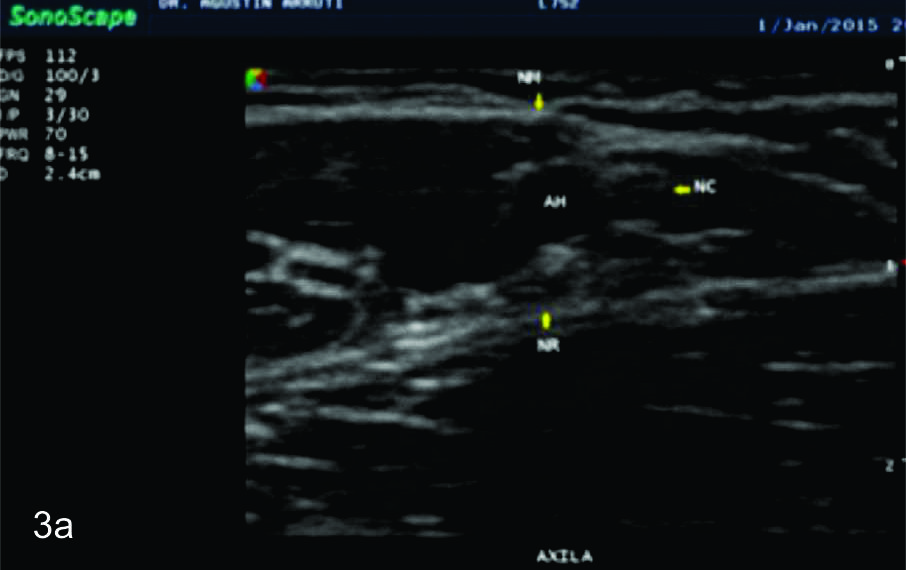

Figura 3

Nervio radial

Serie de cortes axiales del nervio radial desde su origen a nivel del hueco axilar hasta su bifurcación en sus dos ramas terminales a nivel del codo. Se identifica el mismo señalado por flechas amarillas y con las letras NR. AH-arteria humeral, tríceps- músculo tríceps, BA- músculo braquial anterior, CB- músculo coraco braquial, BR- músculo braquiorradial. A- axila, B- tercio proximal del brazo, C- tercio medio del brazo, D- tercio distal del brazo, E- codo, las flechas señalan las dos ramas terminales del nervio radial.